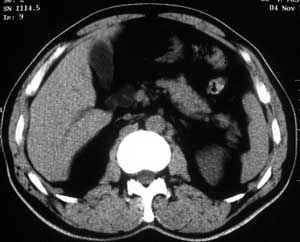

患者,男,57岁,梗阻性黄疸10余天。

这个病例胰头无明显增大,胆总管扩张明显而肝内胆管扩张更不明显,病程较短,

注意到十二指肠乳头明显突出,但尚光滑。分析以下可能性:

1、十二指肠乳头本身的病变,如乳头炎症;

2、急性乳头水肿,胆总管下端结石排石后乳头水肿;

3、壶腹部胆总管下端肿瘤累及十二指肠乳头。

十二指肠乳头粘膜慢性非特异性炎症